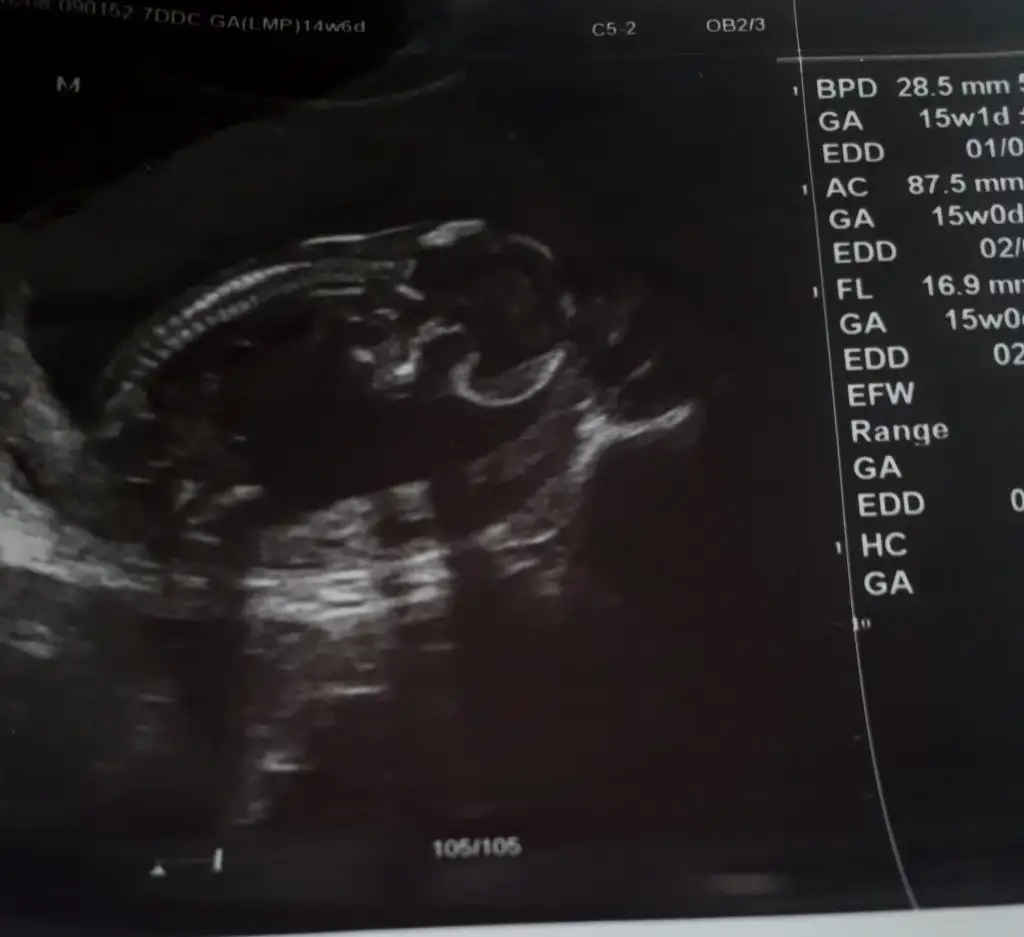

Merhaba arkadaşlar benim için de tahmin yapabilir misiniz rica etsem 13+4 doktor bir tahminde bulundu ama emin olamadı. Sizin yorumlar nelerdir acaba